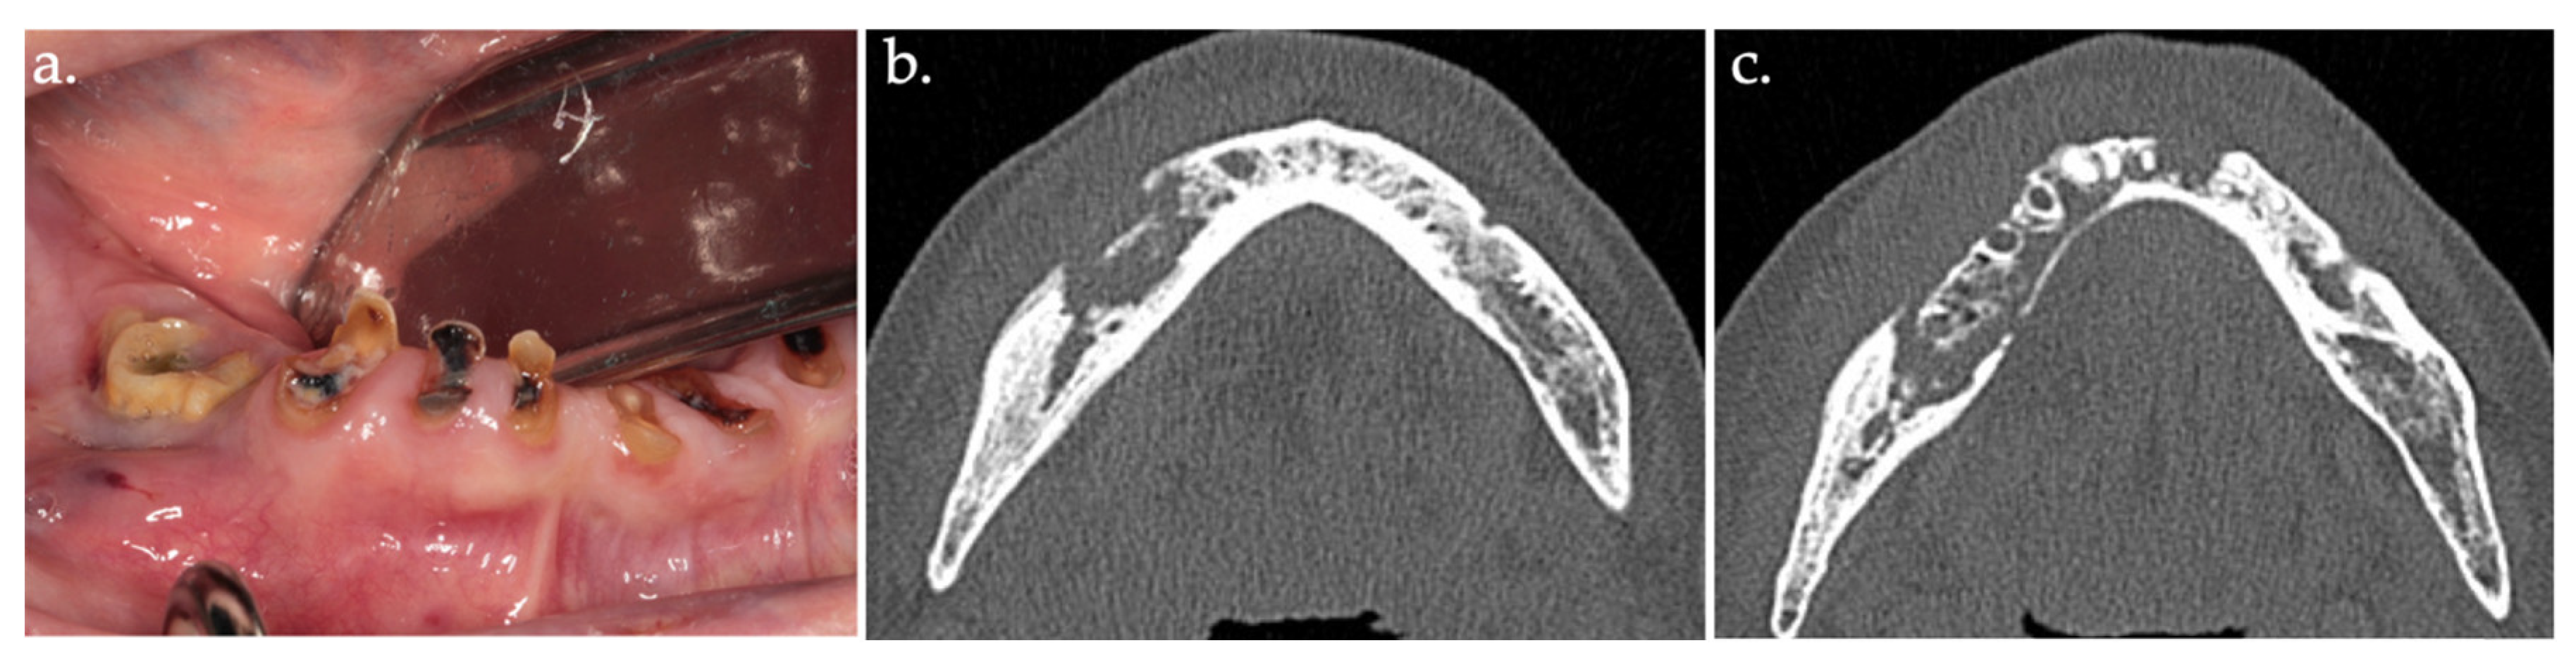

2.2. Autofluorescence-Guided Surgery